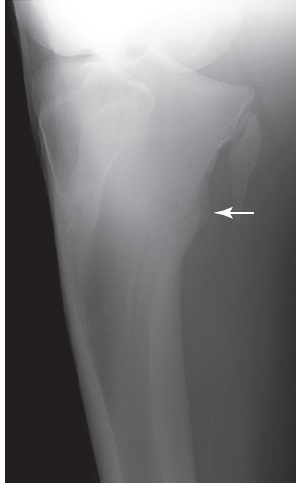

Figure 100-2. A craniolateral-caudomedial oblique radiographic view of a tibia with a midtibial stress fracture. The stress fracture can actually be seen in this horse (arrow), which is unusual because callus normally obscures the fracture.